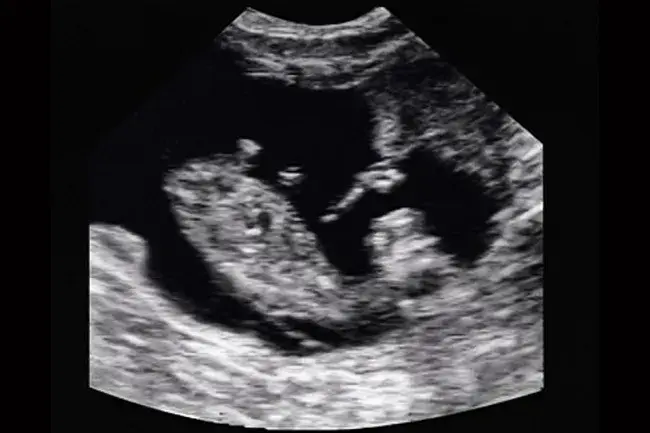

Que la repro se fasse par insémination ou en monte naturelle, les échographies de gestation se font à partir de 35 jours après la fécondation. Les échographies sont suffisamment précises pour assurer des résultats fiables

D’apprécier la viabilité du fœtus

De déterminer les stades de gestation des femelles pleines (1er tiers, milieu, dernier tiers), grâce à l’aspect et à la taille que présentent les embryons. De cette façon on peut prévoir les futures périodes de vêlage avec une bonne précision. C’est une précieuse information pour mettre en lot les femelles et avoir une gestion optimale de leur conduite : rationnement, surveillance des vêlages, etc...

De trouver les jumeauxafin que ces vaches fassent l’objet d’un attention particulière avant et au moment du vêlage.